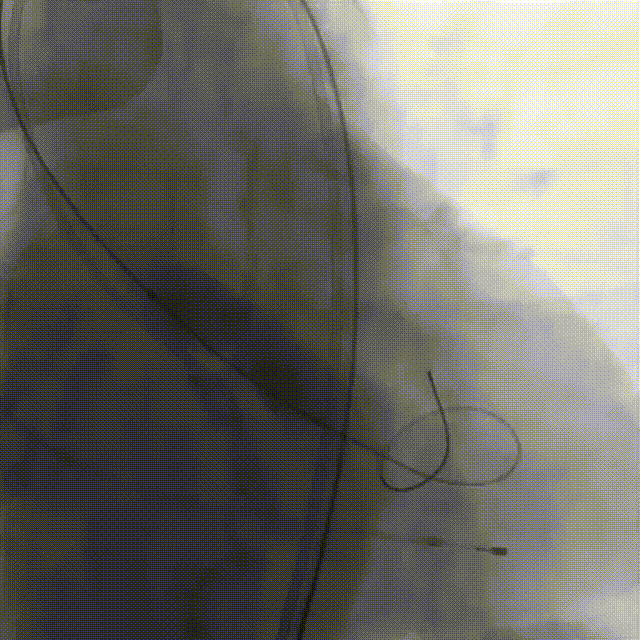

刘煜昊教授 阜外华中心血管病医院(点击查看专家详细简历) 首瓣选耐久,干瓣护航全生命周期管理 2025年ESC专家共识里指出:“推荐第一个瓣膜要选经证实具有长期耐用性的外科瓣膜与经导管瓣膜,以降低再次介入治疗的可能性 ,对于瓣环较小、根据预测有效瓣口面积(EOA)评估存在严重 PPM 风险的患者,可采用主动脉根部扩大术联合 SAVR,或植入环上瓣,对于小瓣环患者自展瓣拥有比较好的血流动力学优势”。 每一次术前评估,都是我们与患者携手面对未知的起点。我们始终以患者全生命周期获益为核心,在瓣膜选择与术式规划中,不只着眼于当下解剖适配,综合评估解剖条件、预期寿命与生活质量。从年轻患者到高龄人群,瓣膜耐久性与血流动力学稳定性始终是决策核心! 陈同峰教授 阜外华中心血管病医院(点击查看专家详细简历) 医学的进步正不断拓宽生命的边界,每一次术前评估都是对生命尊严的深度凝视,技术与人文的交融,让风险不再仅是数字的堆叠,而是成为医者与患者共同面对未知的勇气见证。术中瓣膜释放结束,到了导管测压的时候,我惊喜:瓣膜不错啊,压差为0,这不仅仅得益于瓣膜形态的设计,更是环上瓣及瓣叶材质优质的体现,感受到了 Prostyle A瓣膜在血流动力学上的卓越表现,其采用的抗钙化处理技术有效延长了瓣膜的耐久性,为患者长期生存提供了更可靠的保障。 患者病史 主诉:心慌半月; 门急诊诊断:心悸,冠状动脉粥样硬化性心脏病,心脏瓣膜病,主动脉瓣狭窄,高血压,甲状腺术后; 现病史:半月前无明显诱因出现心慌,呈间断性,伴心悸、出汗,伴头晕,无咳嗽、咳痰,无恶心、呕吐,无双下肢水肿,无放射痛及意识障碍,休息约几分钟后可自行缓解,症状反复发作,遂来我院就诊。 术前超声提示:室间隔增厚;主动脉瓣退行性变并重度狭窄;升主动脉明显增宽;室间隔增厚。 术前CT 三叶瓣,轻度钙化集中在无窦和左窦瓣叶边缘,主动脉根部直径19.3mm,LVOT直径17.7mm,LVOT向下收窄; 窦部正常,VTC空间足够,冠脉风险低; 左室腔小,收缩末径20-25mm,“自杀左室”,循环崩溃风险高;主动脉瓣环水平夹角71.1°,横位心,过弓和跨瓣存在一定困难,备snare。 外周双侧入路内径可,双侧入路能够支持20F大鞘通过,右股低分叉。 手术策略 推荐右侧股动脉为主入路,左侧为辅助入路,右股分叉上方1cm穿刺;推荐选择AV23瓣膜,18mm球囊预扩,左右重叠位:LAO 7° CAU 35°;左冠切线位:LAO 27° CRA 16°;右窦居中位:LAO 18° CAU 9°;备Snare,建议ECMO/CPB湿备,术前术中积极补液,警惕循环崩溃风险。 手术过程 在右股动脉穿刺建立通路后,顺利送入大鞘,经食道超声及血管造影确认路径稳定。18mm球囊预扩过程中,患者血压一度下降,迅速完成扩张并立即植入AV23 ProStyle A®瓣膜。瓣膜精准释放于目标位置,超声显示无明显反流及瓣周漏,血流动力学即刻改善。 主动脉根部造影 18mm球囊预扩少量反流 输送系统柔顺跨瓣 精准定位 平稳释放 80%工作位观索位置合适 释放后导管测压,压差由术前53mmHg降为0mmHg 最终造影瓣膜位置形态良好,冠脉灌注良好,无明显瓣周漏 ProStyle A®预装干瓣——助力临床最优化解决方案: 轻松过弓,精准可控:该病例为横位心,在未使用snare的情况下,过弓和跨瓣柔顺,较细的尺寸+柔顺的输送系统通过性能得到了很好的验证; 平衡的收腰设计:该病例瓣环较小且左室腔小,AV23瓣膜的平衡收腰设计既确保了锚定安全性,又保证了EOA,有效降低了循环崩溃风险,而术后0mmHg的压差的表现更加证明了优秀的血流动力学,提高了瓣膜的耐久性; 预装干瓣 便捷顺安:金仕生物专利抗钙化技术运用纳米技术去除组织内的细胞碎片和磷脂,封闭游离醛基,从根本上阻断了瓣膜钙化的多项因素,显著提升了瓣膜的耐久性;同时,相比较传统戊二醛保存方式,干式存储最大限度的保留心包的亲水亲油平衡,还原组织天然曲柔性,进一步保障了瓣叶开合,保证长期耐久性。 专家简介 王小虎 阜外华中心血管病医院(点击查看专家详细简历) 陈冲 阜外华中心血管病医院(点击查看专家详细简历) 赵一品 阜外华中心血管病医院(点击查看专家详细简历)